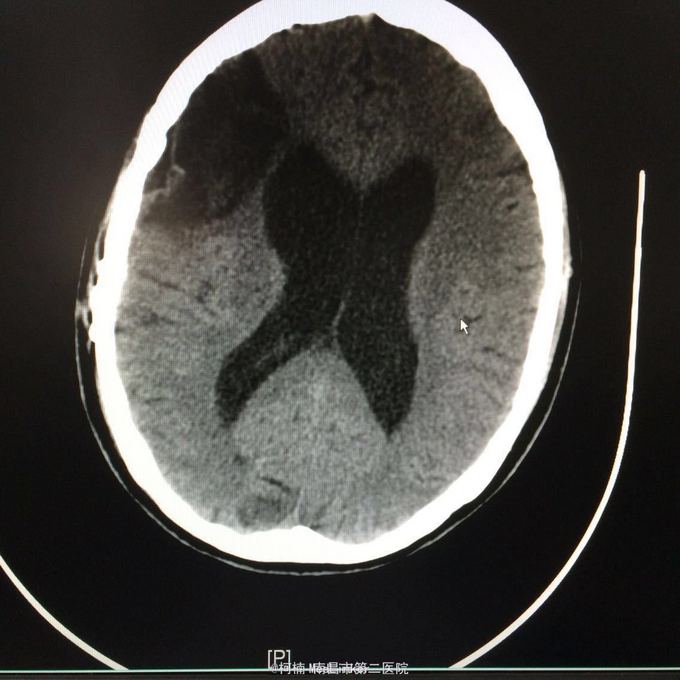

主诉:头痛2年,加重2月 病史:2年前无明显诱因出现头痛,主要为右侧额颞叶胀痛,近两个月来上述症状加重,遂至当地医院行头颅CT提示:右侧额颞叶类圆形异常信号,考虑脑膜瘤合并出血。

神经系统查体阴性 辅助检查:头颅CT提示右侧额颞骨板下肿物伴瘤卒中考虑脑外源性脑膜瘤